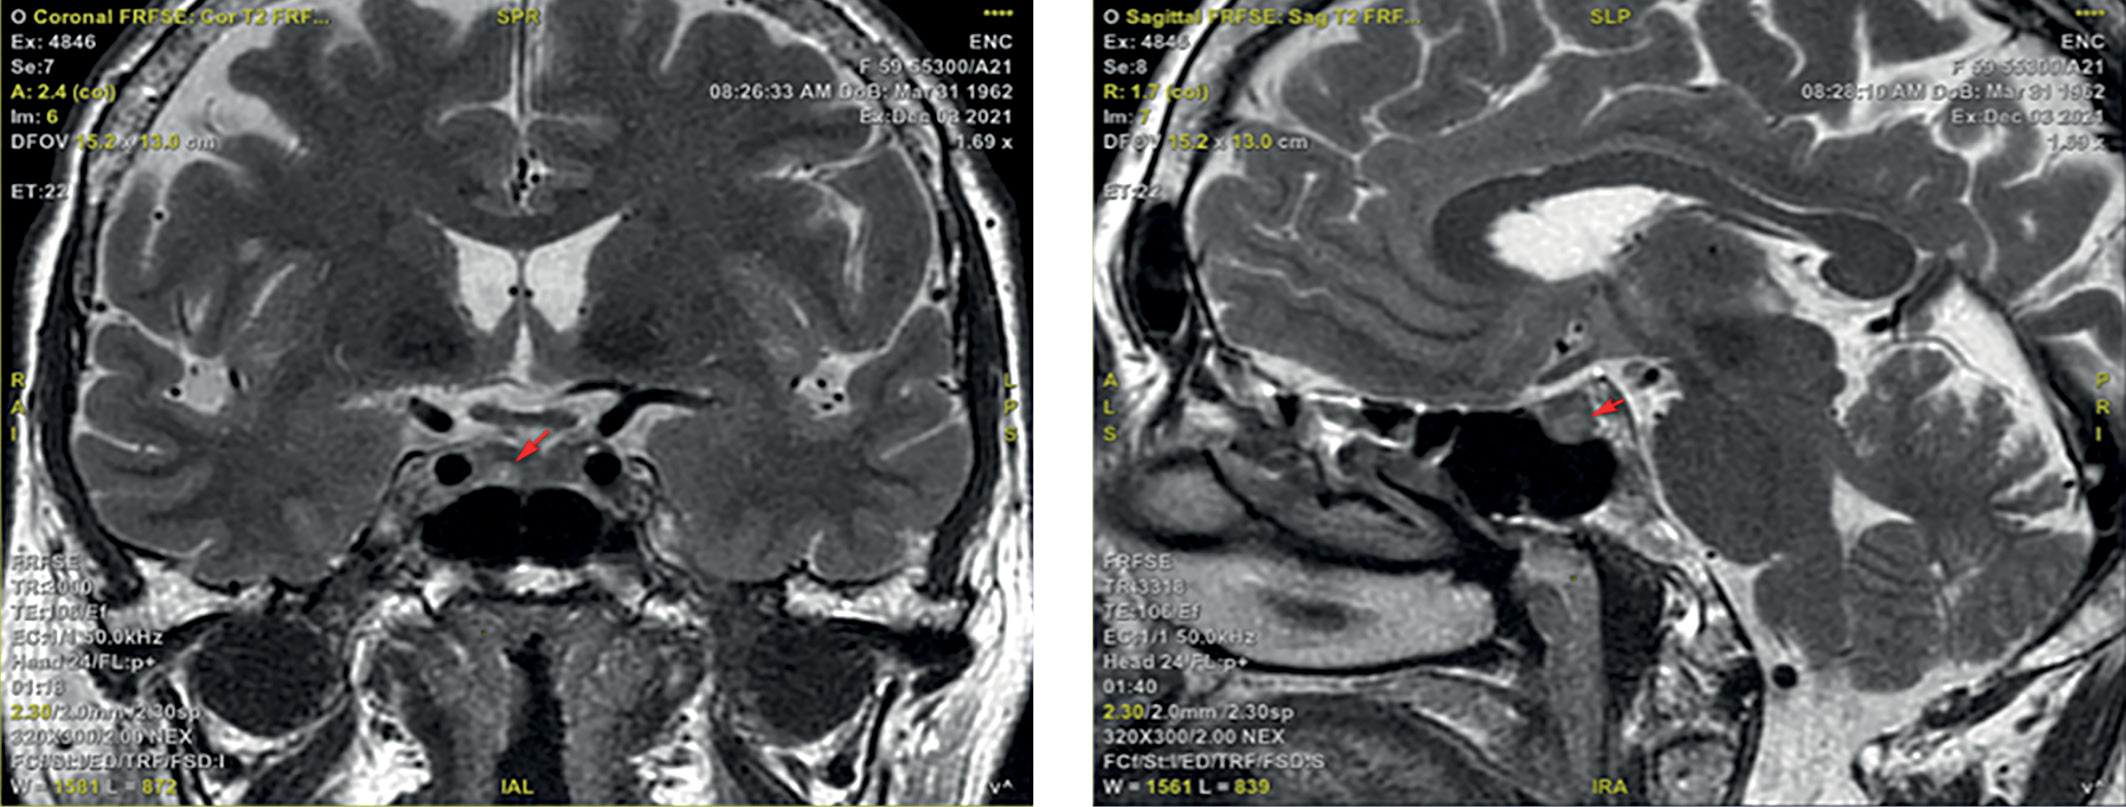

3. Рисунок 3. МРТ головного мозга во фронтальной и сагиттальной проекциях. Красными метками отмечено образование гипофиза. | |